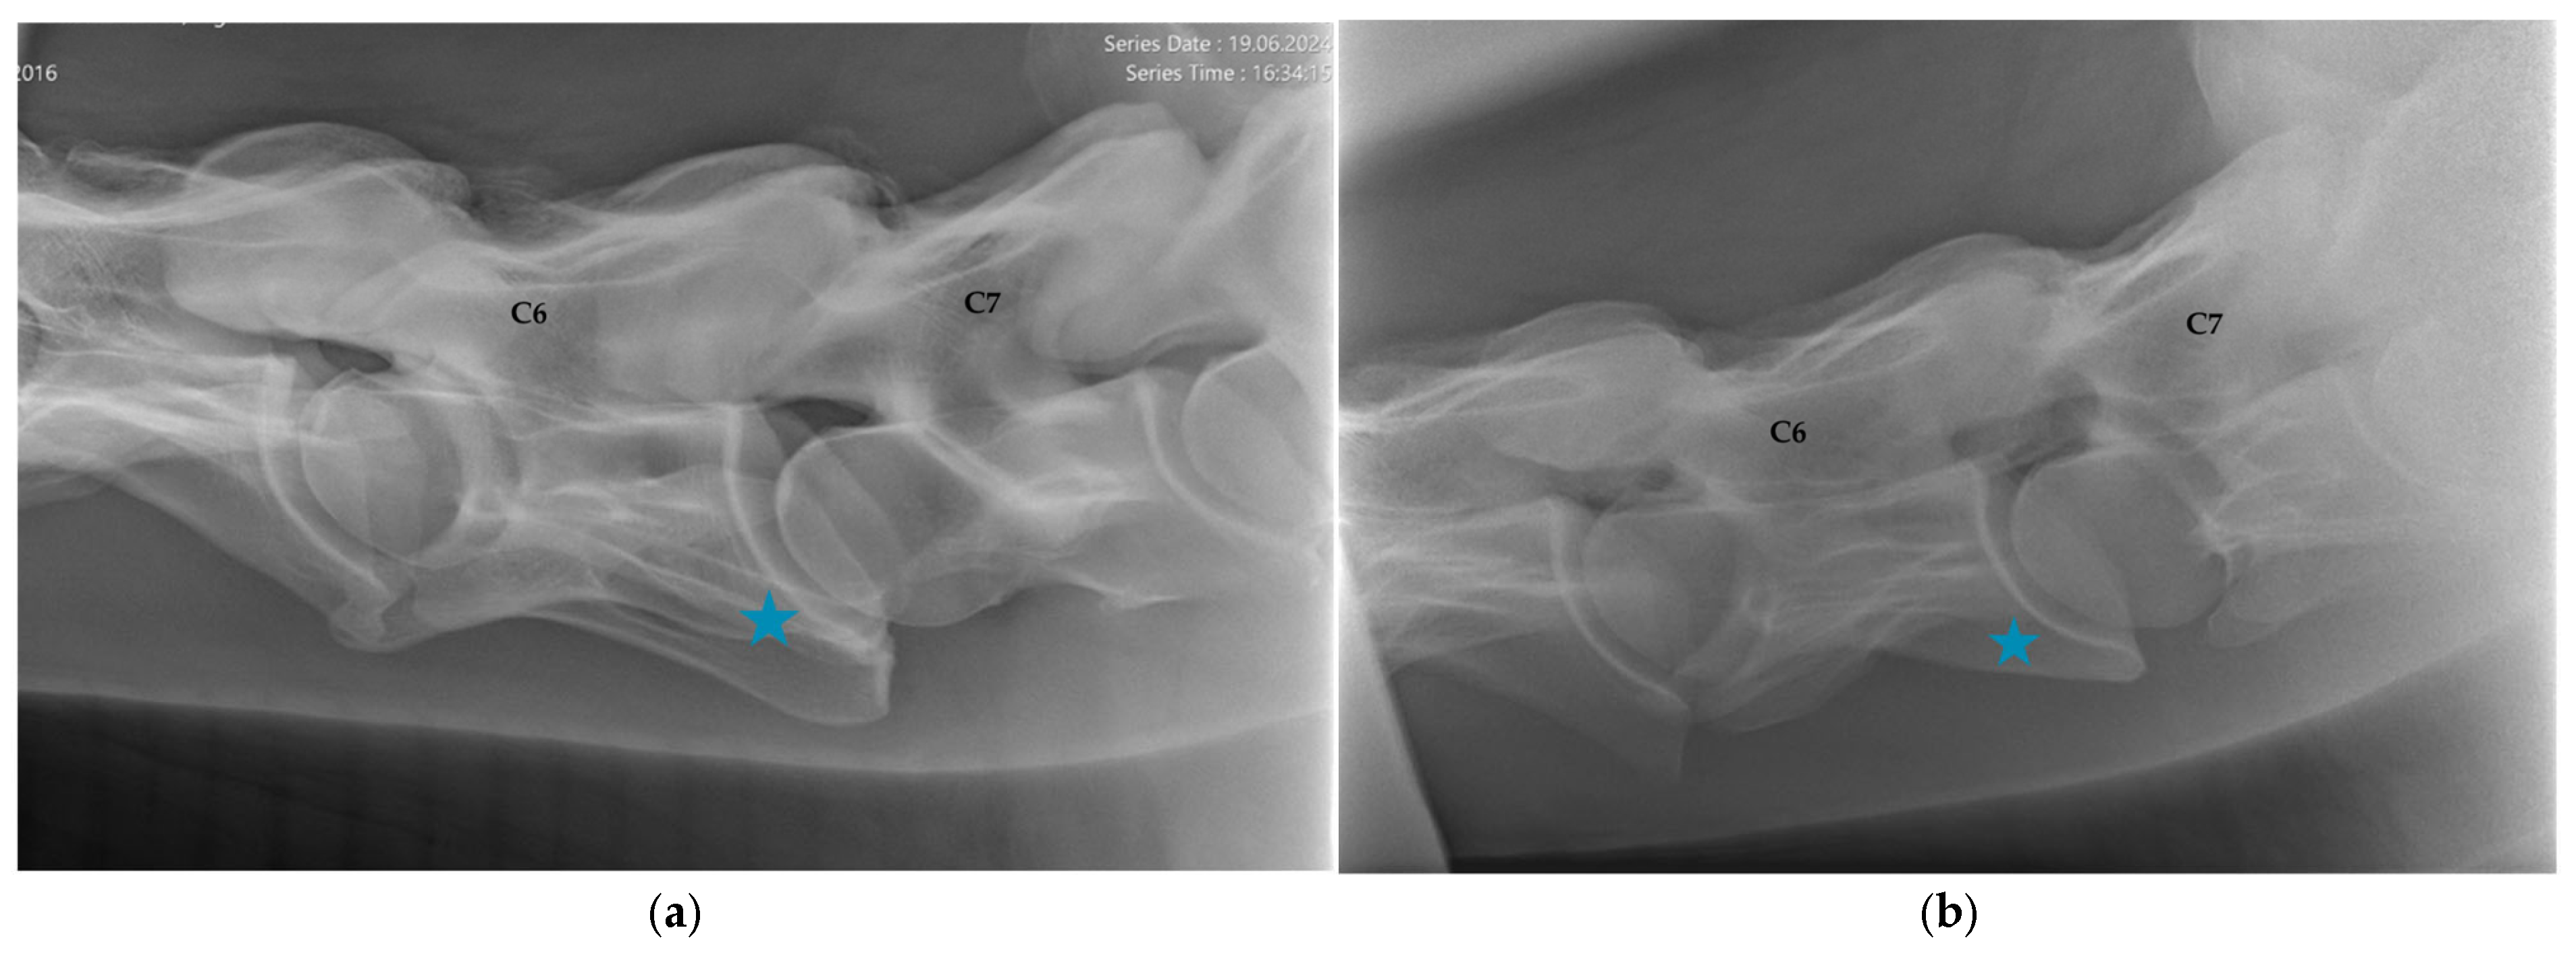

2.1.2. Radiographic Assessment

- Group 1 = normal: no periarticular new bone formation at ventral margins of APJ, intervertebral foramina clearly visible.

- Group 2 = mild APM: minimal/equivocal enlargement and sclerosis of APJ with mild osteophytosis ventrally, intervertebral foramina open/slightly obscured by new bone formation.

- Group 3 = moderate/severe APM: clear enlargement and sclerosis of APJ with moderate osteophytosis ventrally, significant reduction/loss of intervertebral foramina.